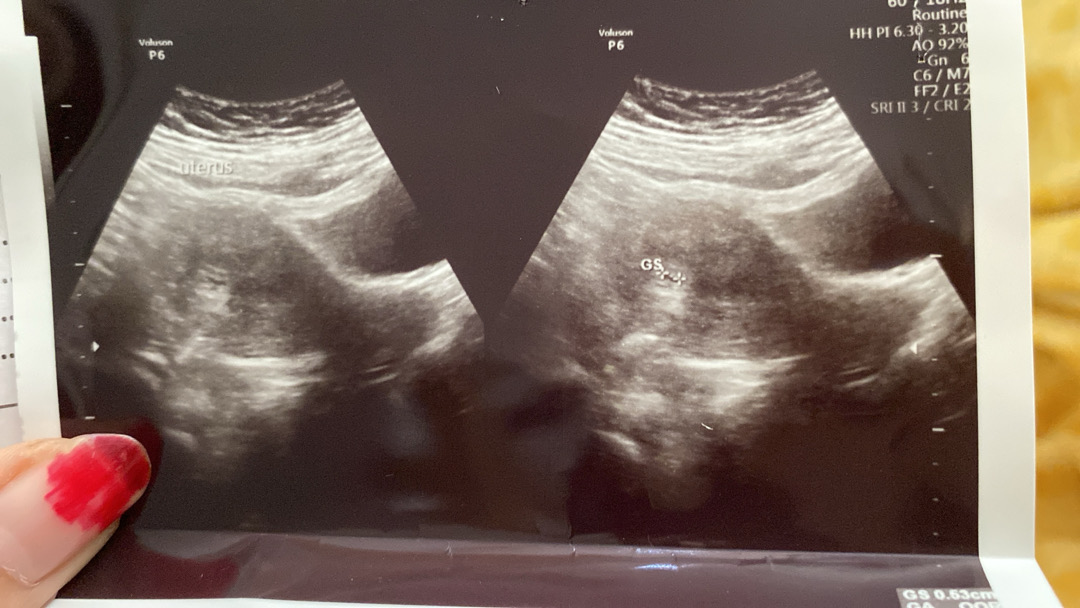

Bundaa mau curhat, aku tuh hpht 29 desember.. setelah itu ga dapet haid lg.. hampir setiap hari aku test pack hasilnya negatif terus.. 9 februari ditestpack negatif, usg juga kosong gada apa”.. tgl 12 nya testpack positif, ditanggal 15 usg udh kliatan segitu, kecil banget tp umurnya klo berdasarkan hpht 7 minggu bund.. kayaknya usia sebenarnya ga segitu ga sih bund? Kaya masih umur 1/2 minggu🤧

Saya 6 minggu juga segede biji jagung bunda

Coba usg transvaginal bun biasanya hamil muda direkomendasiin sm dokter buat usg transv karna kalau usg perut pasti gak bakal keliatan, gunanya jg buat mastiin kehamilan kita bun

Kalo bunda siklus haidnya agak panjang biasanya perkembangan janinnya jg jd agak lama dr hpht. Aku pas periksa 6w jg harus pake usg tv krn masih kecil bgt blm terlihat. Semoga pas usg selanjutnya udah keliatan janinnya ya bun. Selalu afirmasi positif aja ke dede utun